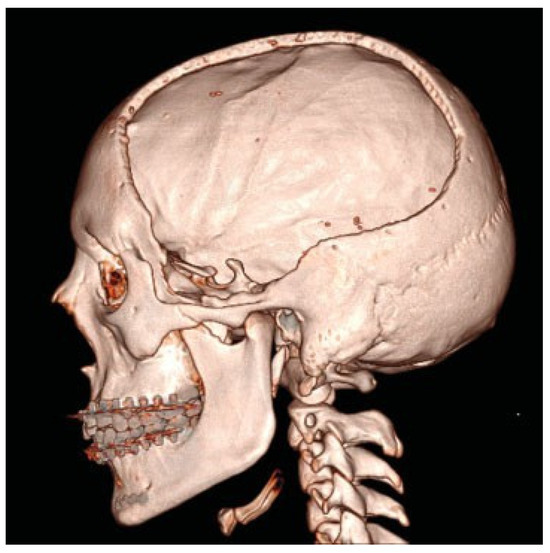

De Water, V.R.; dos Santos Rubio, E.J.; Schouten, J.W.; Koudstaal, M.J. Deformation of a Titanium Calvarial Implant following Trauma: A Case Report. Craniomaxillofac. Trauma Reconstr. 2016, 9, 158-161. https://doi.org/10.1055/s-0035-1567810